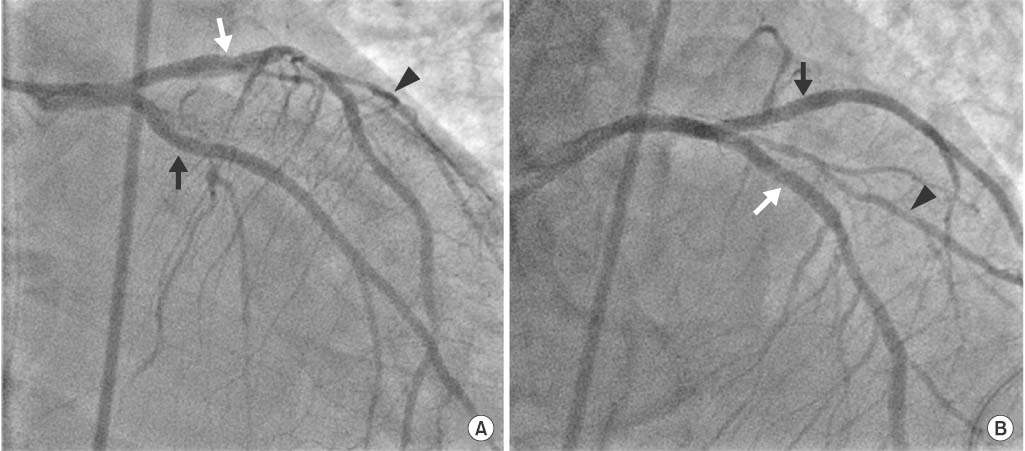

Fig. 3Initial coronary angiogram. (A) Caudal view of left system angiogram shows total occlusion of the proximal left anterior descending artery (white arrow) and left circumflex artery (black arrow). There is seen diagonal artery (arrow head) with thrombosis in myocardial infarction flow II. (B) Left anterior oblique view of coronary angiogram shows total occlusion of the proximal RCA (arrow).

An urgent coronary angiogram (CAG) revealed three-vessel coronary disease; total occlusions of the proximal left anterior descending artery (LAD), the proximal left circumflex artery (LCX) and the proximal right coronary artery (RCA) (

Fig. 3). Fortunately, the flow to the diagonal artery (D1) from LAD was preserved with thrombosis in myocardial infarction (TIMI) flow II. We inserted intra-aortic balloon pump (IABP) first and undertook percutaneous coronary intervention (PCI) on the proximal LAD, which was the culprit vessel for this ST-elevation myocardial infarction (STEMI). The LAD lesion was passed easily and smoothly with a 0.014 floppy guidewire (Balanced Middle Weight, Abbott Vascular, Santa Clara, CA, USA). An everolimus-eluting stent (Xience prime, Abbott Vascular). 3.0×23 mm was deployed after ballooning, resulting in TIMI flow III, but did not show any collateral flow from LAD to LCX territory (

These simultaneous thromboses of the left coronary arteries were supported by angiographic findings that both lesions were passed easily by soft guidewire, and there were no collateral flows from other vessels to LAD and LCX territories. However, RCA lesion would be considered as CTO, as it was too hard for the guidewire to pass through, and multiple fine collaterals from the left coronary arteries to RCA territory were suspected after intervention.